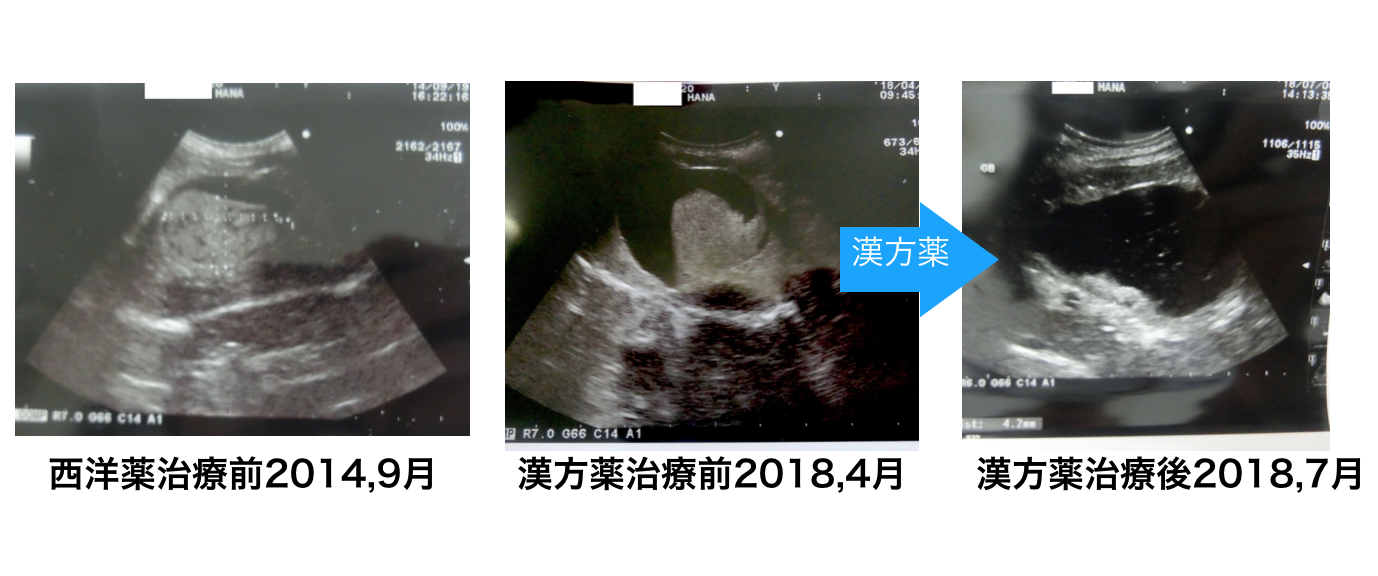

犬 胆泥症 原因-胆泥 をかたちづくっているのは コレステロール や 黄疸色素 ( ビリルビン )、 カルシウム などの微細な 結晶 が 胆嚢壁 から分泌される 粘液 に包まれたものと考えられますが、他にも 炎症 によっこんにちは。獣医師の清水いと世です。 今回は、わんちゃんの胆泥症について説明します。 前編は、胆泥症の原因や検査方法や症状について、後編は治療や予防方法について説明します。 犬の胆泥

胆泥症・胆石症について 胆嚢は、胆汁を産生し貯留する器官です。 胆汁には、脂肪を分解し水に溶けやすい状態に(乳化)する役割を持っています。 胆嚢に貯えられた胆汁は、元々サラサラの水胆泥を生じさせた原因や疑われる原因があれば、それを取り除きます。 そのために、 犬の胆泥症 <前編> で説明した原因追及のための検査結果が重要になります。 肝臓の異常が認められるので